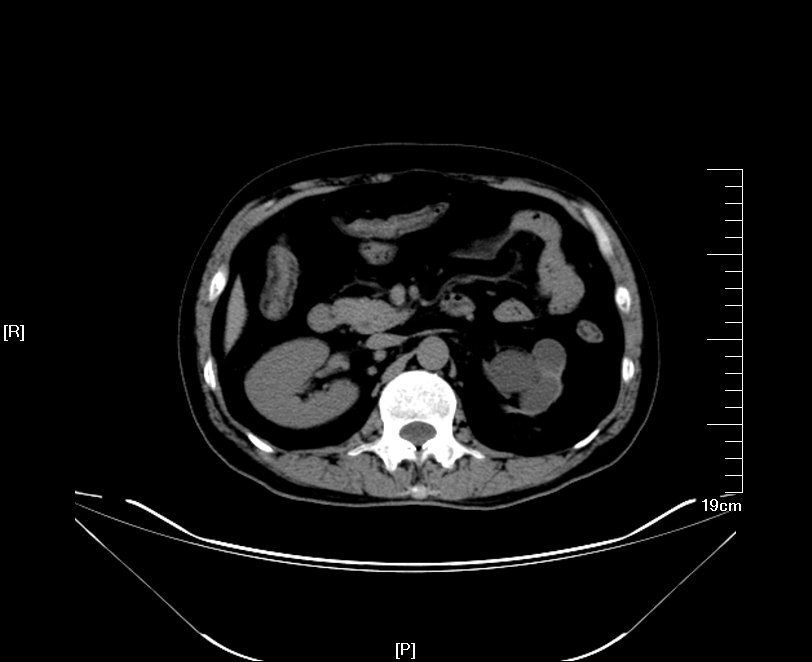

2016年09月手术患者,男性,83岁,太仓人,双侧腰酸不适五年伴体检发现双侧输尿管结石一周入院,五年来患者自觉双侧腰酸,一直未予重视,近期自觉双下肢浮肿且左侧腰痛明显加剧,遂参加社区免费体检时发现双侧输尿管结石遂来院就诊,CT:右肾萎缩无功能,左侧肾脏代偿性增大,左肾积水扩张,双侧输尿管结石,左侧约1.5cm,右侧约2.0cm GFR:左侧41.27ml/min,右侧5.2ml/min。肾功能:Cr 571umol/L;术前诊断:双侧输尿管结石 右肾萎缩 右肾无功能 左肾积水,鉴于右输尿管结石梗阻时间太长,右肾已几乎无功能,萎缩固缩,且肾功能已失代偿,遂只能急症先输尿管镜处理左输尿管结石,保护左侧肾脏,待肾功能稳定后再处理右侧输尿管结石及右肾,患者预后不容乐观。

CT检查提示:右肾萎缩无功能,左侧肾脏代偿性增大,左肾积水扩张,双侧输尿管结石